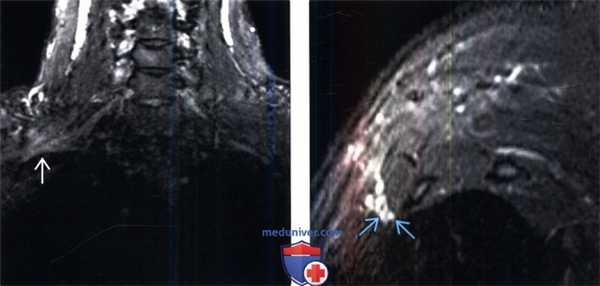

(Слева) На фронтальном STIR МР-И у профессионального музыканта (барабанщика) с клиникой правостороннего неврологического СВАГК определяется патологическое усиление интенсивности Т2-сигнала плечевого сплетения в пределах ВА.

(Справа) На косо-сагиттальном STIR МР-И (профессионального барабанщика) на уровне ВА отмечается некоторая гиперинтенсивность Т2-сигнала отдельных пучков волокон нижнего ствола плечевого сплетения, соответствующая клинической картине нижней плечевой плексопатии.